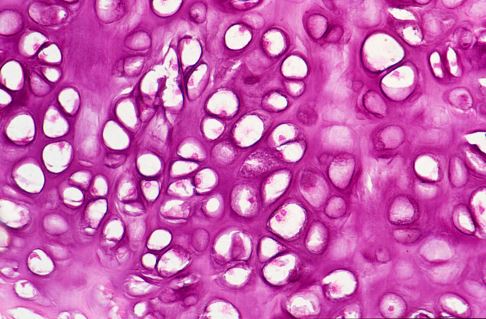

Hyaliner Gelenkknorpel unter dem Mikroskop: Gut sichtbar sind die Chondrozyten (Knorpelzellen), die von der Knorpelmatrix umgeben werden. © Josep Maria Barres, iStock

Faserknorpel unter dem Mikroskop: Im Vergleich zum hyalinen Knorpel sind weniger Chondrozyten sichtbar. Der Aufbau des Ersatzknorpels ist durch Kollagenfasern gekennzeichnet. © Josep Maria Barres, iStock

Knorpelbildende Maßnahmen mit Anfrischung des Knochens unterhalb des geschädigten Knorpels eignen sich besser zur Faserknorpelbildung. Diese Maßnahme nennt sich Mikrofrakturierung, da die Knochenoberfläche mit einem spitzen Werkzeug minimal aufgebrochen wird. Das darunterliegende Knochengewebe ist gut durchblutet. Es entstehen leicht blutende, kleine Verletzungen im geschädigten Gelenkbereich. Diese Verletzungen lösen eine natürliche Verschorfung des Gelenks durch das geronnene Blut aus. Blut und Knochenmark mit differenzierungsfähigen Stammzellen wandern in den Bereich des zerstörten Knorpels ein.

Unter dieser Schorfschicht kommt es dann zur Bildung eines faserigen Ersatzknorpels mit etwas veränderten Gleiteigenschaften. Der Patient sollte sein Hüftgelenk in der Heilungsphase entlasten.